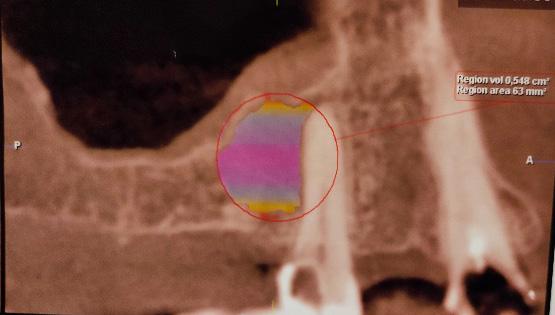

Aplicación de biomateriales post exeresis en un quiste inflamatorio radicular

Application of biomaterials post exeresis of a root inflammatory cyst

Javier Adrián Burgos, Renia Hurtado, Fabián Galindo, Juan Delgado....................................................97-106